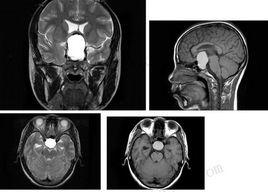

![放射醫學[臨床醫學專業] 放射醫學[臨床醫學專業]](/img/6/ba3/nBnauM3X0IjN1kTO3IjN0ETN1UTM1QDN5MjM5ADMwAjMwUzLyYzLygzLt92YucmbvRWdo5Cd0FmLxE2LvoDc0RHa.jpg)